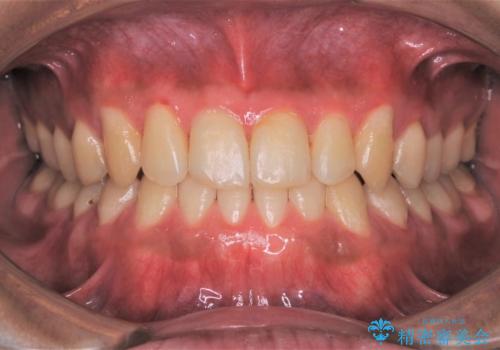

数年ぶりに歯のクリーニング(PMTC)